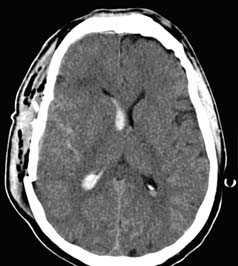

Методом выбора при диагностике ушиба головного мозга является КТ головного мозга. На КТ определяют ограниченную зону пониженной плотности, возможны переломы костей свода черепа, субарахноидальное кровоизлияние. При ушибе мозга средней степени тяжести на КТ или спиральной КТ в большинстве случаев выявляют очаговые изменения (некомпактно расположенные зоны пониженной плотности с небольшими участками повышенной плотности).

При ушибе тяжелой степени на КТ определяются зоны неоднородного повышения плотности (чередование участков повышенной и пониженной плотности). Перифокальный отек головного мозга сильно выражен. Формируется гиподенсивная дорожка в область ближайшего отдела бокового желудочка. Через нее происходит сброс жидкости с продуктами распада крови и мозговой ткани.

На КТ определяют двояковыпуклую, реже плоско-выпуклую ограниченною зону повышенной плотности, которая примыкает к своду черепа и локализируется в пределах одной или двух долей. Однако, если источников кровотечения несколько, зона повышенной плотности может быть значительного размера и иметь серповидной форму.